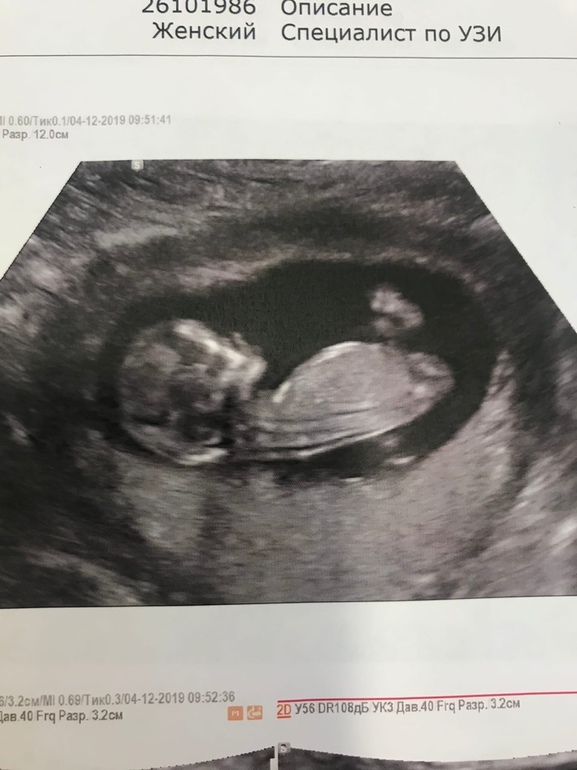

( мне кажется тут пуповина между ног)Вот то что я высмотрела на видео на Первых секундах.

Рядом ножка и бугорок , второй ножки не видно.

Рядом ножка и бугорок , второй ножки не видно.Вот фото сына